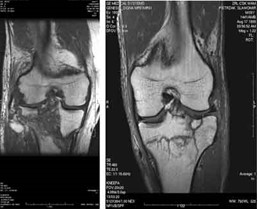

Którą metodą i w której płaszczyźnie zostało wykonane badanie stawu kolanowego zobrazowane na zdjęciach?

A. MR, w płaszczyźnie czołowej.

B. TK, w płaszczyźnie czołowej.

C. TK, w płaszczyźnie strzałkowej.

D. MR, w płaszczyźnie strzałkowej.